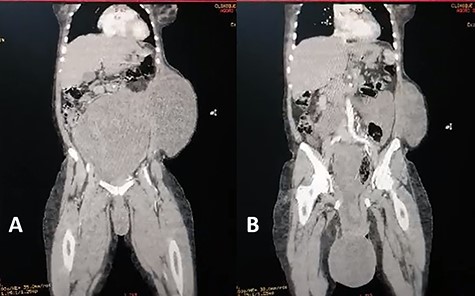

Coronal view of abdominal enhanced CT scan showing: (A) large, well-limited and slightly enhanced abdominopelvic mass. (B) protusion of the abdominopelvic mass trough perineum.

A 40-year-old gravida 4 para 4 was referred to our centre for an abdominal and perineal mass that gradually enlarged over the past 3 years. She complained of abdominal distension, slow transit with 1–2 stools per week, and difficulty in voiding. There was no abdominal pain. She lost 8 kg over the past 3 years. On physical examination, the patient had a large, firm and indolent abdominal mass that emerged through an incisional hernia of the abdominal wall. We also noted a second mass, measuring 40 cm and occupying the internal part of the gluteal region. Its pedicle extended into the pelvis through the right ischiorectal fossa (Fig. 1). Perineal examination revealed a grade IV hysterocele. Computed tomography (CT) showed a huge, well-demarcated solid, homogeneous mass with moderate enhancement occupying the abdomen and pelvis herniating through the perineum (Fig. 2). The core needle biopsy findings were consistent with myxoid neurofibroma. Exploratory laparotomy showed a firm multilobed mass (Fig. 3) that contracted intimate adhesions with the pelvic colon, right ureter and rectum. Resection was performed without organ involvement through a combined perineal approach. Tumour resection was macroscopically completed except in the perineum, where the tumour was left (R2 resection) to avoid anal sphincter injury. The operative specimen weighed 5.842 kg. Histological analysis showed a spindle cell tumour with a myxoid matrix without atypia or mitosis. On immunochemistry, the tumour was negative for PS 100 and CD 117 and positive for nuclear β-catenin and smooth muscle actin. It was diagnosed as a desmoid tumour. During the immediate postoperative period, wound infection and partial dehiscence were noted. Flatus and liquid stool incontinence were also observed. The incontinence completely improved during the 12th postoperative week. Adjuvant treatment with tamoxifen at an initial dose of 150 mg/day and indomethacin (100 mg per day) was given for the incomplete excision (R2). Tamoxifen was tolerated by the patient and continued for 24 months. A follow-up examination 12 months postoperatively documented a complete response. Indomethacin was discontinued after 4 months due to gastralgia. Colonoscopy was performed in the third postoperative month, and there was no polyadenomatosis, confirming the sporadic character of the desmoid tumour. After 36 months of follow-up, no recurrence was observed.